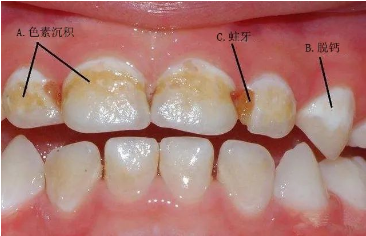

初期症状:牙齿本来应该是同个颜色,当表面开始有黑点或脱钙的白点出现,或是某处老是塞住食物,表示此处牙齿的牙釉质已遭到破坏。

中期症状:龋齿若没有加以控制及治疗,会由牙釉质慢慢延伸到牙本质,形成窝洞,此时对甜食及冷热的刺激会很敏感,容易感到酸痛。或是食物一卡进牙缝,就觉得不舒服,但清掉后,不舒服就解除了。